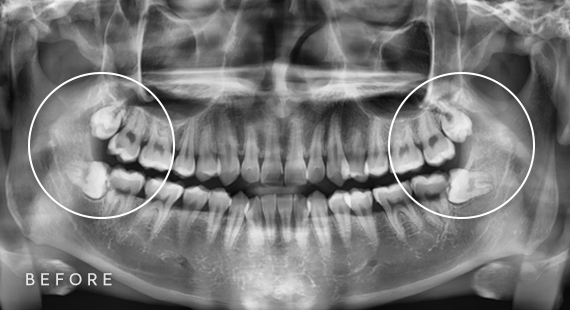

사랑니 발치